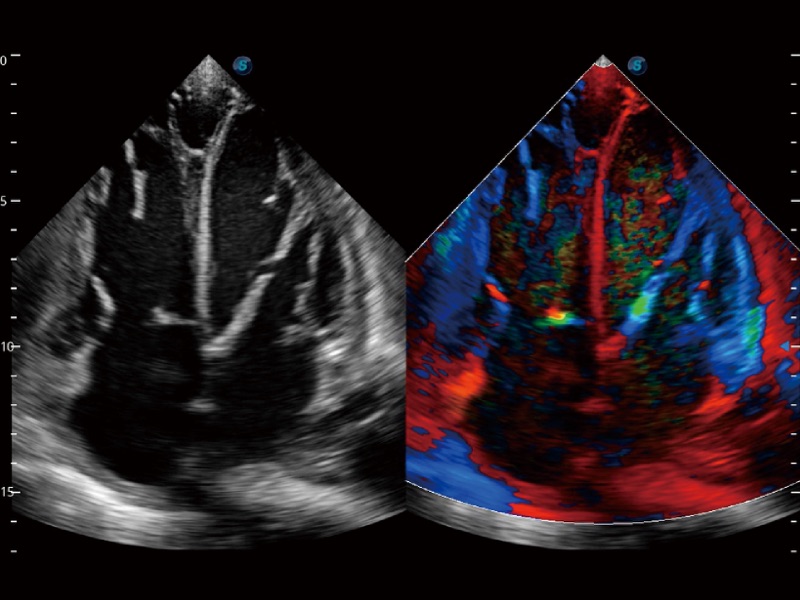

高分辨率血流成像技術(shù)提高了對(duì)低速血流信號(hào)的檢測(cè)能力。在提高空間分辨率的同時(shí),也克服了血流外溢現(xiàn)象,為用戶(hù)提供更加真實(shí)的血流動(dòng)力學(xué)信息。

心血管應(yīng)用